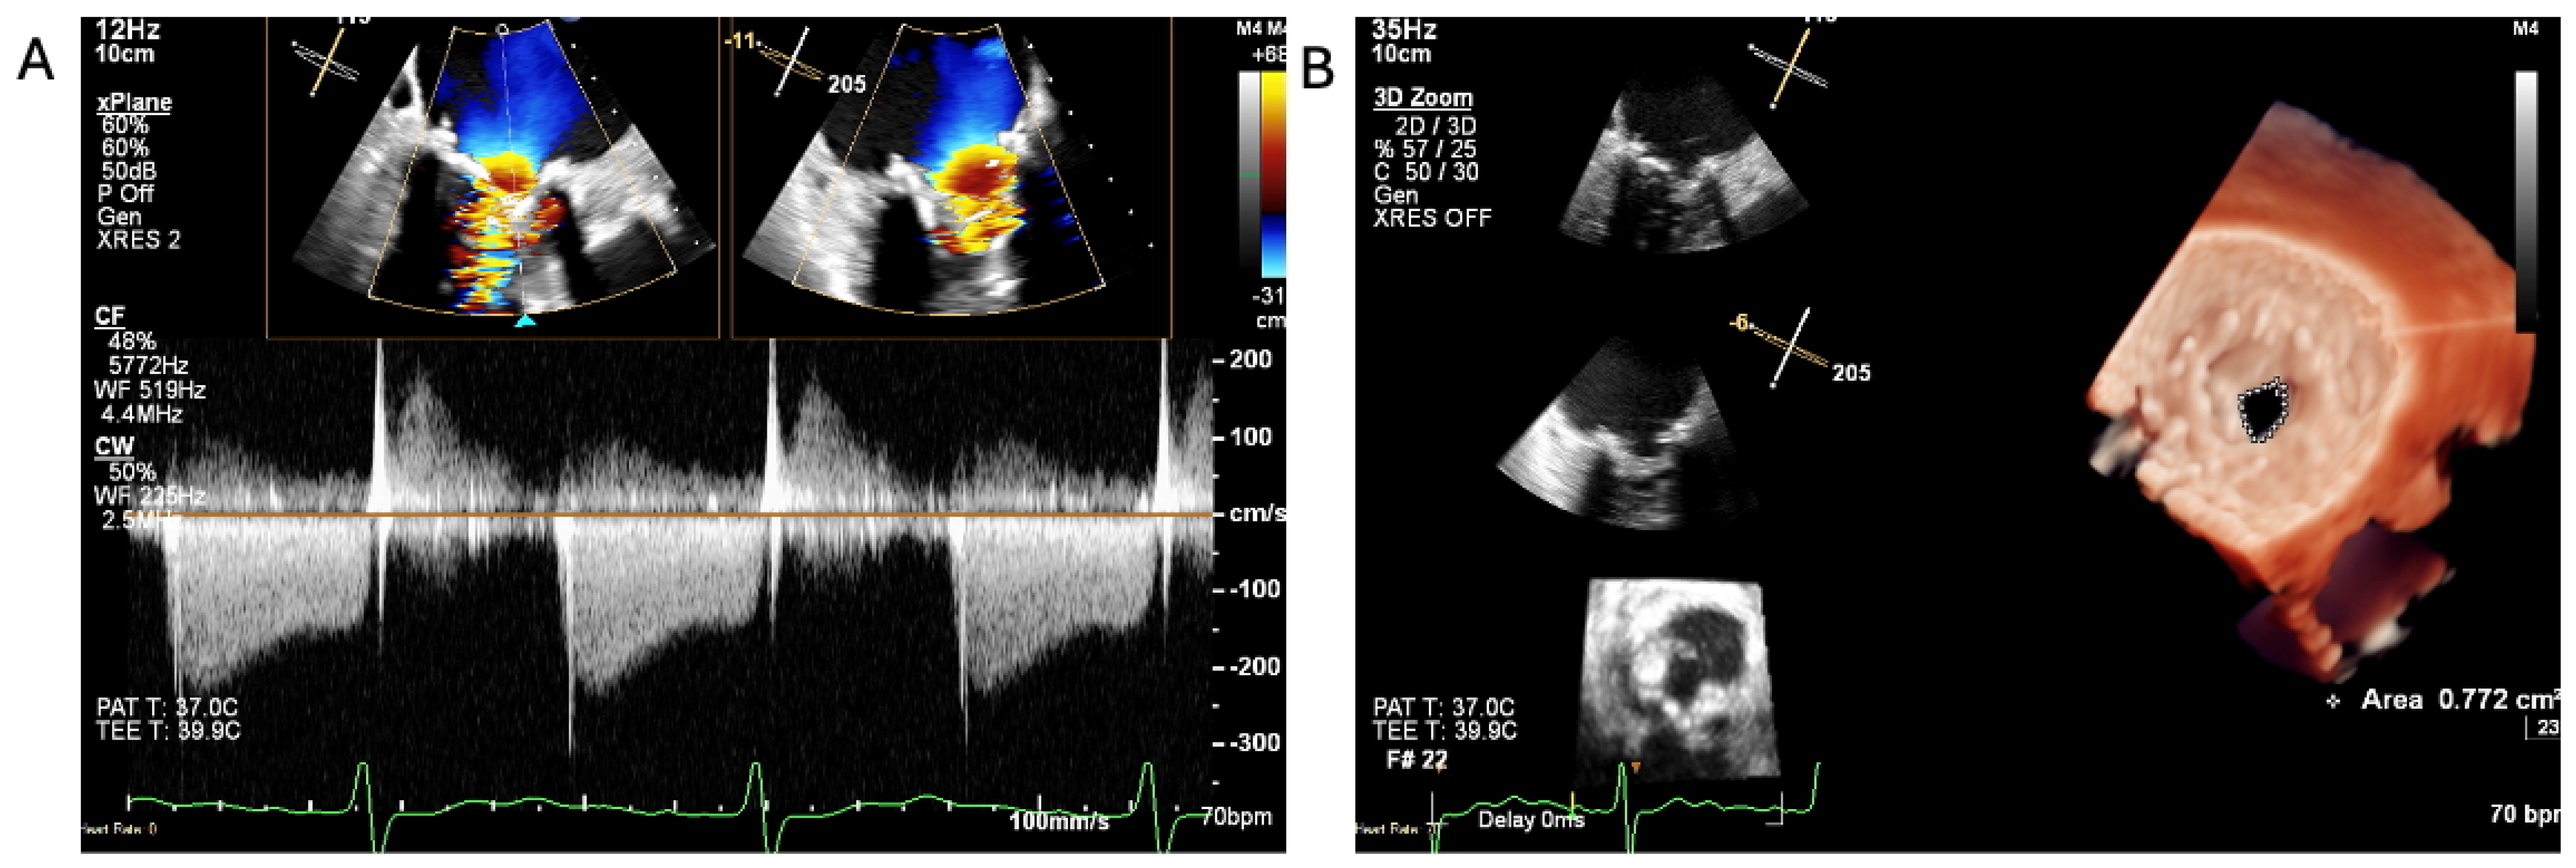

2.4. When the Diagnosis of IE Is Only Confirmed by the Tissue Culture of the Removed Degenerated tAVR